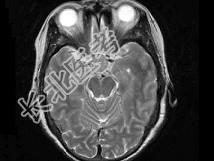

- 单项选择题女,55岁, 1年前出现头痛,头昏, 症状间断性加重,半年后出现视物模糊, 且视力逐步下降,以右侧为甚, 根据所提供图像,最可能的诊断是 ( )

B、颅咽管瘤

C、垂体腺瘤

D、脑膜瘤